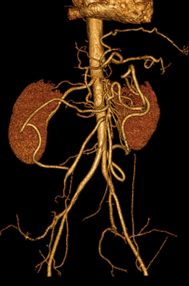

Micronodules

COCHE E. - 2021 - UCL

Cardio-thoracique DES SPECIALITE